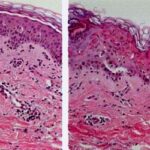

Histopathology. EM is considered the prototype of the vacuolar form of interface dermatitis . The early changes include vacuolization of the basal cell layer; tagging of lymphocytes along the dermal-epidermal junction; and a sparse, superficial, perivascular lymphoid infiltrate . Necrosis of individual keratinocytes in the basal unit occurs, which is the hallmark of EM. Because of its acute nature, there is an orthokeratotic stratum corneum. Mild spongiosis, papillary dermal edema, and extravasation of red blood cells are seen. As the lesion becomes more developed, there is a moderate lichenoid infiltrate of Iymphohistiocytes at the dermal-epidermal junction with exocytosis. More apoptotic keratinocytes within and above the basal epidermal layer are present. The |

intensity of epidermal necrosis varies from vacuolated individual keratinocytes surrounded by lymphocytes (satellite cell necrosis) at the basal unit to confluent necrosis in association with intraepidermal and subepidermal vesicles. The dermal infiltrate comprises lymphocytes and histiocytes. Eosinophils may also be present. Although one study has noted a significant number of eosinophils in drug-induced EM, this has not been noted by others. In the authors’ estimation, a generous number of eosinophils exclude EM. One study has found that an acrosyringium concentration of apoptotic keratinocytes in EM is a clue to a drug etiology . In early lesions of SJSITEN, apoptotic keratinocytes are observed scattered in the basal layer of the epidermis. In established lesions, there are numerous necrotic keratinocytes, even full-thickness epidermal necrosis, and a subepidermal bulla. The dermal inflammatory infiltrate is sparser in TEN than in EM (Fig. 9-278). Extravasated erythrocytes are commonly found within the blister cavity. Melanophages within the papillary dermis occur in late lesions. Eccrine epithelium shows a variety of changes from basal cell apoptosis to necrosis of the duct. |

In general, EM shows less epidermal necrosis, more dermal inflammation, and exocytosis, whereas SJS and TEN reveal more epidermal necrosis, less dermal inflammation, and exocytosis. However, due to the overlapping histologic features among EM, SJS, and TEN, histologic examination-while important for recognizing the spectrum of disorders-is not reliable for classifying the disease. Correlation with clinical presentation is essential. |